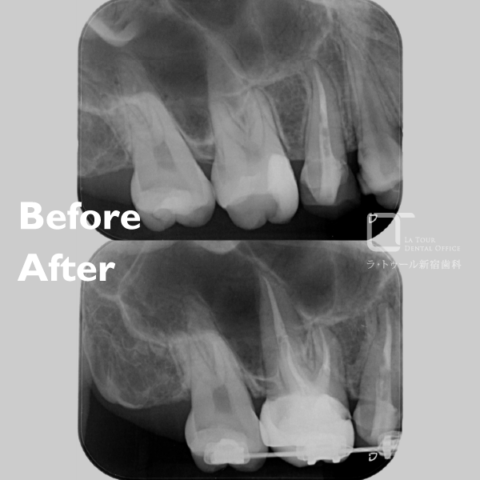

セラミック治療の治療例です。金属の使用を避けたいとのご希望から、メタルフリー治療を目的に来院されました。セラミックは生体親和性が高く、金属を使用しないため金属アレルギーのリスクが少なく、安心して使用できる素材です。当院にて虫歯治療を行い、セラミックによる修復を実施しました。通院回数の負担を考慮し、上下同時での治療をご希望されたため、同日に治療を行っています。接着の精度を高めるため、治療時にはラバーダムを使用しています。また、オキシガードは過酸化物と還元剤による化学重合反応により、歯科接着用レジンセメント表面の未重合層を硬化させる材料です。未重合層を空気から遮断することで確実な硬化を促します。

上顎

術前から術後までの治療の流れ

下顎